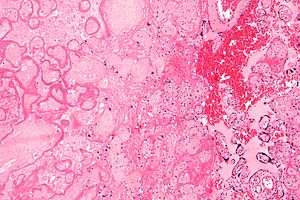

| Micrograph of a placental infarct. H&E stain. | |

A placental infarction results from the interruption of blood supply to a part of the placenta, causing its cells to die.

Small placental infarcts, especially at the edge of the placental disc, are considered to be normal at term. Large placental infarcts are associated with vascular abnormalities, e.g. hypertrophic decidual vasculopathy, as seen in hypertension.[1] Very large infarcts lead to placental insufficiency and may result in fetal death.

Maternal floor infarcts are not considered to be true placental infarcts, as they result from deposition of fibrin around the chorionic villi, i.e. perivillous fibrin deposition.